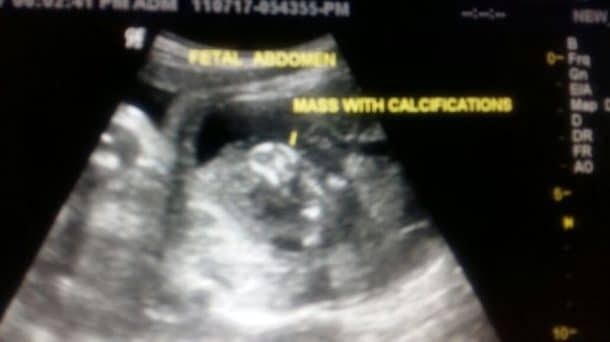

Les scanners avaient décelé une anomalie

Le bébé parasite a été envoyé à une équipe de recherche qui va mener plus de tests. Il s’agissait d’un garçon de 7 cm et qui pesait 150 g, dont le développement avait connu des malformations. L’anomalie avait été repérée à neuf jours de la naissance, lors d’une visite de routine de la maman à l’hôpital. Le radiologue n’était pas certain de ce qu’il s’agissait, il a fallu attendre la naissance du bébé pour comprendre qu’il avait son jumeau à l’intérieur de lui. Il était bien entendu impossible pour le bébé parasite de survivre, car malgré son cerveau, il n’avait pas développé d’os du crâne et ne possédait pas tous les organes vitaux.